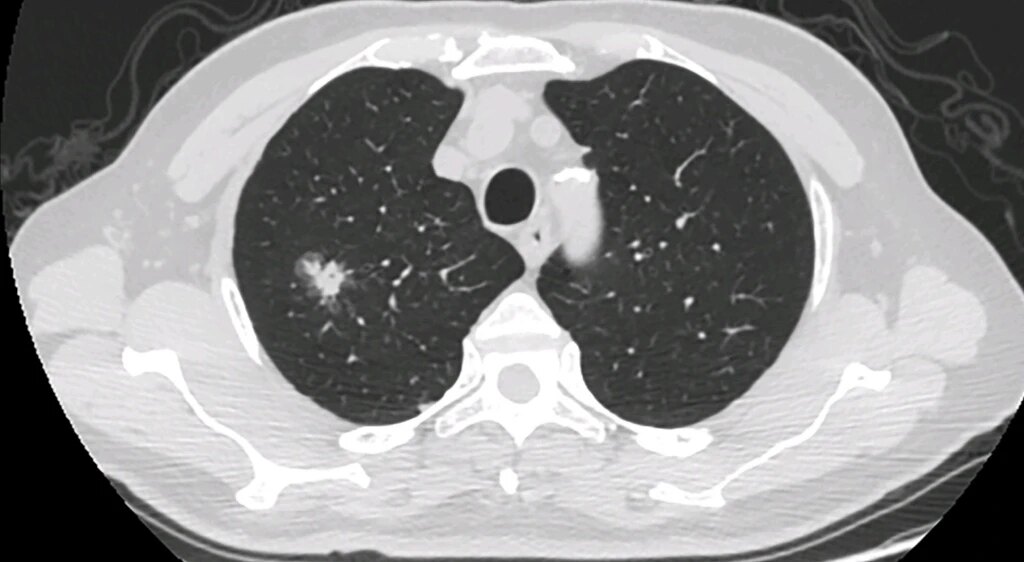

肺部磨玻璃结节是指在胸部CT扫描中呈现出密度增高的亚实性肺部病灶,它们可以是良性的,也可以是恶性的。人们在谈到肺部磨玻璃结节时可能会感到害怕,主要是因为其中一部分可能会发展成为早期肺癌。但是,磨玻璃结节本身只是影像学上的一种描述,不代表疾病本身或者预示着病情走向。

肺部磨玻璃结节有良性病变和恶性肿瘤之分。良性病变可能包括肺部炎症、真菌感染、炭末沉积等,而恶性病变可能是肺腺癌。肺腺癌又分为不同的阶段,包括浸润前阶段、微小浸润腺癌和浸润腺癌。其中,浸润前阶段包括不典型腺瘤样增生和原位癌,而这些在新的胸部肿瘤分类中已被划分为良性病变。

对于肺部磨玻璃结节的管理,通常推荐首次发现时以定期复查胸部CT为主要手段,不建议立即手术干预。如果结节增大或实性比例增加,或者影像学提示可能是微小浸润腺癌、浸润腺癌,那么可以考虑外科手术。对于小于10毫米甚至20毫米的纯磨玻璃结节,多数是原位癌、微小浸润腺癌,如果及时切除,五年生存率几乎为百分之百。